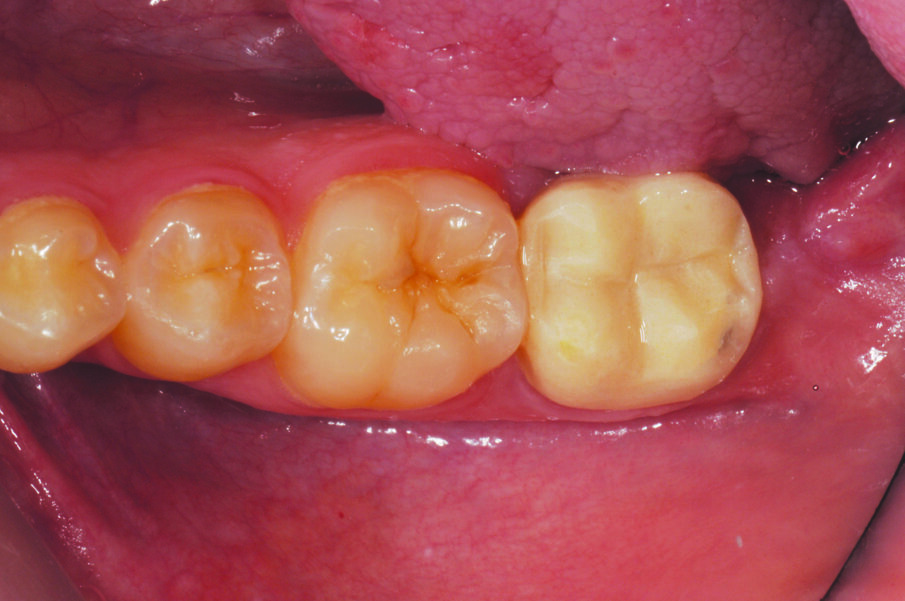

Fig. 1: Initial Situation with a molar tooth in need of endodontic treatment and subsequent crown placement.